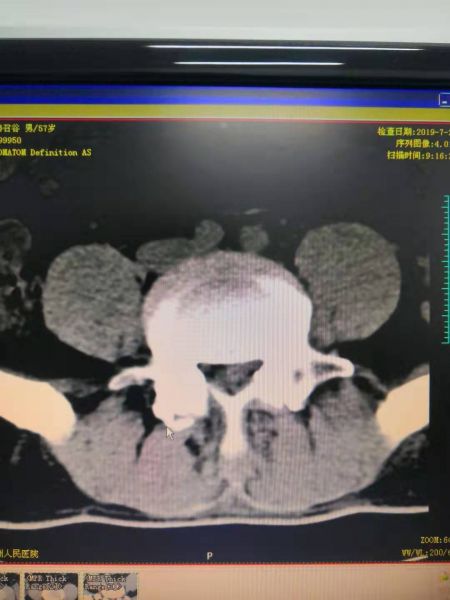

术前L4/5向左侧脱出